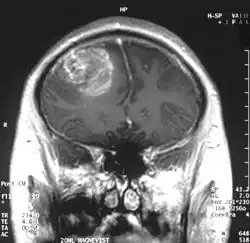

Kumaravel Somasundaram (Born: 8 October 1962) is an Indian cancer biologist and a professor at the Department of Microbiology and Cell Biology of the Indian Institute of Science. Known for his studies on the therapeutics of Glioblastoma, Somasunderam is an elected fellow of all the three major Indian science academies namely, the National Academy of Sciences, India, the Indian Academy of Sciences and the Indian National Science Academy. The Department of Biotechnology of the Government of India awarded him the National Bioscience Award for Career Development, one of the highest Indian science awards, for his contributions to biosciences in 2006.

Somasundaram's work is centered around the studies of oncoviruses, tumor suppressor genes, gliomas and microRNAs and he has done advanced research on glioblastoma, an aggressive form of cancer affecting the brain.[8][9] The group led by him is engaged in work concerning the determination of the role of cellular tumor antigen p53 in glioma, regulating the protein, p73 in cervical cancer patients, using Adenovirus early region 1A, a tumor suppressor gene, the analytical study of BRCA1 gene in breast cancer and the analysis and regulation of SV2A, a synaptic vesicle protein.[3] He demonstrated that glioblastoma spreads rapidly by producing macrophage colony-stimulating factor (MCSF) in large quantities which in turn stimulate the growth of blood vessels in the tumor.[10] He proposed that the MCSF interacted with the anti-tumor microglial cells of the human body and induced them to produce Insulin-like growth factor-binding protein 1 (IGFBP1), thereby impairing the capacity of microglial cells to fight the tumor cells, a process he called befriending. The discovery of this new molecule, IGFBP1 and its role in glioma angiogenesis, led to a collaborative investigation which involved four research institutions namely National Institute of Mental Health and Neuro Sciences, Sri Sathya Sai Institute of Higher Medical Sciences and Institute for Functional Genomics (INSERM) of the University of Montpellier, apart from the IISc.[11] The research team led by Somasundaram and Phillipe Marin of INSERM validated the earlier findings and proposed a new therapeutic protocol for glioblastoma which targeted IGFBP1, rather than Vascular endothelial growth factor (VEGF) which earlier treatment methods attacked.[12] The researchers, later, released their findings through a paper, Glioblastoma-derived Macrophage Colony Stimulating Factor (MCSF) Induces Microglial Release of Insulin-like Growth Factor-Binding Protein 1 (IGFBP1) to Promote Angiogenesis, published in the Journal of Biological Chemistry.[13] Work is in progress at his laboratory for developing biomarkers (twenty genes of which is named gene X, have already been discovered)[14] for which detailed study is being conducted on microRNA, DNA methylation, modifications of chromatin and gene fusions.[4][15] His studies have been documented by way of a number of articles[16][17][note 1] and ResearchGate, an online repository of scientific articles has listed 178 of them.[18] He has also conducted workshops[19][20][21] including the Workshop on Next Generation Sequencing organized by the Council of Scientific and Industrial Research in November 2013[22] and has delivered invited or plenary speeches at various conferences and seminars[23] and the 5th annual meeting of the Proteomics Society, India held in September 2013 was one among them.[24]